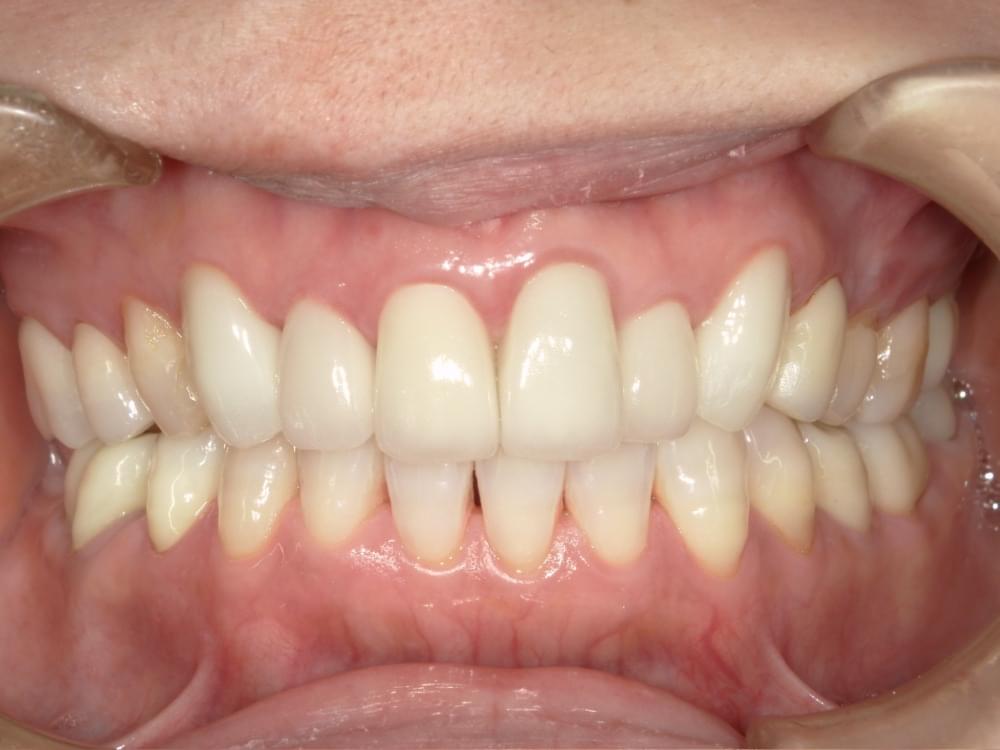

歯周病治療プログラムの治療例5

治療の概要

治療内容

行動科学に基づき、「自分の歯は自分で守る」という意識改革や行動変容を促しながら、スケーリングや歯ブラシ・フロス指導を行いました。

治療期間・回数・時間

1.5ヶ月・5回・計5時間

費用

29,500円+税

リスク・副作用

歯肉の痛み・出血